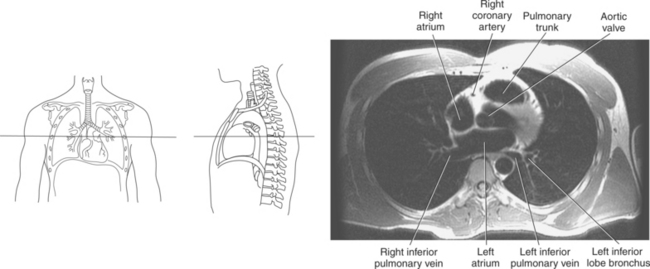

The right atrium forms the right border of the heart and receives deoxygenated blood from the body via the superior and inferior venae cavae and from the coronary sinus and cardiac veins that drain the myocardium. A small muscular embryonic appendage, the right auricle, projects upward and toward the left from the right atrium, covering the root of the aorta (Figure 6.40). The right ventricle lies on the diaphragm and comprises the largest portion of the anterior surface of the heart. It receives deoxygenated blood from the right atrium and forces it into the pulmonary trunk for conveyance to the lungs. Projecting off the inferior surface of the ventricular walls are conical-shaped projections of cardiac muscle called papillary muscles that anchor the cusps of the tricuspid valve to the right ventricle (Figure 6.39). The left atrium lies posterior to the right atrium and is the most posterior surface of the heart. It also has an embryonic appendage, the left auricle, that projects to the left of the pulmonary trunk over the superior surface of the heart. The left atrium receives oxygenated blood directly from the lungs via the four pulmonary veins (two on each side). The left ventricle forms the apex, left border, and most of the inferior surface of the heart. It receives oxygenated blood from the left atrium and pumps it into the aorta for distribution throughout the systemic circuit. The myocardium of the left ventricle is normally three times thicker than that of the right ventricle, reflecting the force necessary to pump blood to the distant sites of the systemic circulation (Figures 6.41 through 6.52). Two papillary muscles project from the ventricular walls to anchor the bicuspid valve to the ventricle (Figures 6.39 and 6.47).

Figure 6.43 Axial, T1-weighted MR scan of left atrium.

Key: RV, Right ventricle; LV, left ventricle; LA, left atrium; RA, right atrium.

Blood travels to and from the heart through the great vessels, which include the aorta, pulmonary arteries and veins, and superior and inferior venae cavae (Figures 6.54 and 6.55). The aorta is the largest artery of the body and can be divided into the ascending aorta, aortic arch, and descending aorta. The ascending aorta begins at the base of the left ventricle at the level of the sternal angle, then curves superiorly and posteriorly as the aortic arch over the root of the left lung. The top of the aortic arch is approximately at T3 (Figures 6.56 and 6.57). The arch continues as the descending aorta posterior to the left bronchus and pulmonary trunk, on the left side of the vertebral body of T4 (Figures 6.58 and 6.59). The descending aorta passes slightly anterior and to the left of the vertebral column as it descends through the thoracic and abdominal cavities (Figure 6.60). While in the thoracic cavity, the descending aorta is commonly called the thoracic aorta, and while in the abdominal cavity, it is called the abdominal aorta. The pulmonary trunk is the origin of the right and left pulmonary arteries and lies entirely within the pericardial sac. It arises from the right ventricle and ascends in front of the ascending aorta, courses posteriorly and to the left, where it bifurcates at the level of the sternal angle (T4) into the right and left pulmonary arteries (Figures 6.61 through 6.63). The pulmonary trunk is attached to the aortic arch by a fibrous cord called the ligamentum arteriosum, the remnant of an important fetal blood vessel (ductus arteriosus) that links the pulmonary and systemic circuits during fetal development (Figures 6.54 and 6.61). The right pulmonary artery courses laterally, posterior to the ascending aorta and superior vena cava, and anterior to the esophagus and right mainstem bronchus, to the hilum of the right lung. At the root of the right lung, the right pulmonary artery divides into two branches, with the lower branch supplying the middle and inferior lobes and the upper branch supplying the superior lobe (Figures 6.61 through 6.64). The left pulmonary artery, shorter and smaller than the right, is also the most superior of the pulmonary vessels. It travels horizontally, arching over the left mainstem bronchus, and enters the hilum of the left lung just superior to the left mainstem bronchus (Figures 6.61 through 6.64). Within the lungs, each pulmonary artery descends posterolateral to the main bronchus and divides into lobar and segmental arteries, continuing to branch out and to follow along with the smallest divisions of the bronchial tree (Figures 6.61 and 6.64). Located inferior to the pulmonary arteries are the four pulmonary veins, two each (superior and inferior) extending from each lung to enter the left atrium (Figures 6.54, 6.55, 6.61, and 6.64 through 6.68). They commence in a capillary network along the walls of the alveoli, where they are continuous with the capillaries of the pulmonary arteries. The venous capillaries merge to form small vessels that unite successively to eventually form a single trunk for each lobe: three for the right and two for the left lung. Frequently the trunk from the middle lobe of the right lung unites with the trunk from the upper lobe, forming just two trunks on the right side prior to entering the left atrium. The right superior pulmonary vein collects blood from the upper lobe segments of the right lung and passes anterior and inferior to the right pulmonary artery, behind the superior vena cava. The right inferior pulmonary vein receives blood from the right lower lobes of the lung and crosses behind the right atrium to the left atrium (Figures 6.61 and 6.69 through 6.71). The left superior pulmonary vein receives blood from the left upper lobe of the left lung and courses anterior and inferior to the left main bronchus as it enters the left atrium. The left inferior pulmonary vein drains the inferior lobe of the left lung and passes toward the left atrium anterior to the bronchi (Figures 6.61 and 6.72 through 6.74). The pulmonary veins course more horizontally than the pulmonary arteries and are ultimately oriented toward the left atrium. At the root of the lungs, the pulmonary veins are anterior to the pulmonary arteries, which are anterior to the bronchus. While within the lungs, the branches of the pulmonary arteries are anterior to the bronchi, which are anterior to the pulmonary veins. The superior and inferior venae cavae are the largest veins of the body. The superior vena cava is formed by the junction of the brachiocephalic veins, posterior to the right first costal cartilage, and carries blood from the thorax, upper limbs, head, and neck (Figure 6.24). As it travels inferiorly, it is located posterior and lateral to the ascending aorta before entering the upper portion of the right atrium (Figures 6.54 through 6.59). The inferior vena cava is formed by the junction of the common iliac veins in the pelvis and ascends the abdomen to the right of the abdominal aorta and anterior to the vertebral column. It passes through the caval hiatus of the diaphragm and almost immediately enters the inferior portion of the right atrium (Figures 6.75 and 6.76).